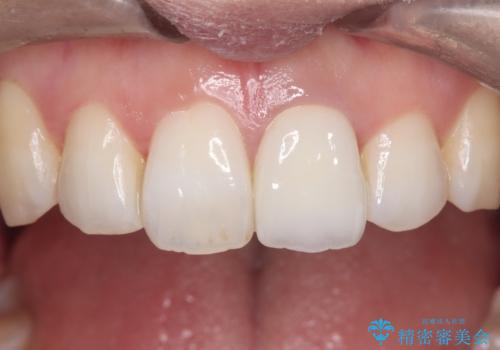

前歯の気になる変色を解消。再根管治療とオールセラミックで自然な美しさへ

担当医 河口智英